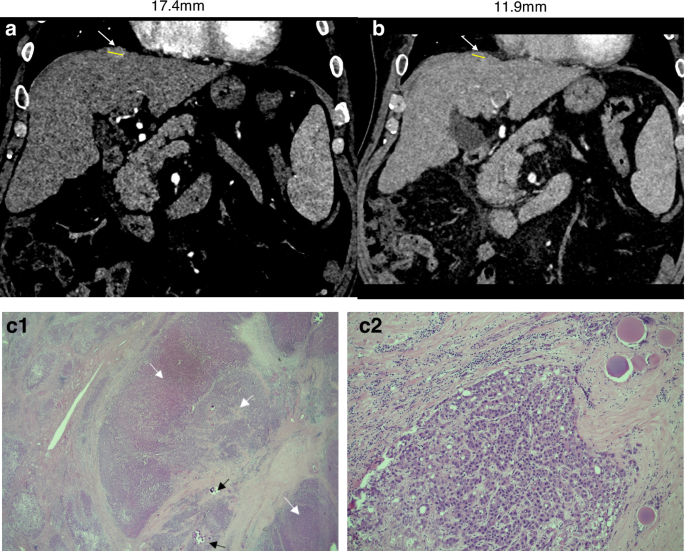

a Pre-SABR CT showing arterially enhancing Segment 4 HCC; (b) 3 months post-SABR CT showing reduction in the lesion size with minimal residual enhancement; (C1) Low power haematoxylin and eosin staining of tumour showing fibrosis, embolization material (black arrows), viable tumour (white arrows), and a background of cirrhosis (left hand side of image). (C2) Higher power view showing viable tumour (embolization material present on right hand side of image).

Post-SABR imaging was available in five patients and was reported by experienced radiologists as showing no evidence of residual active HCC in three patients (Table 1, Fig. 1), indeterminate hyperenhancement with difficulty delineating residual disease from post-radiotherapy changes in one patient (Fig. 2), and active HCC with increased tumour size in one patient. In all five of these cases, viable HCC tumour was subsequently detected in the explant histology.